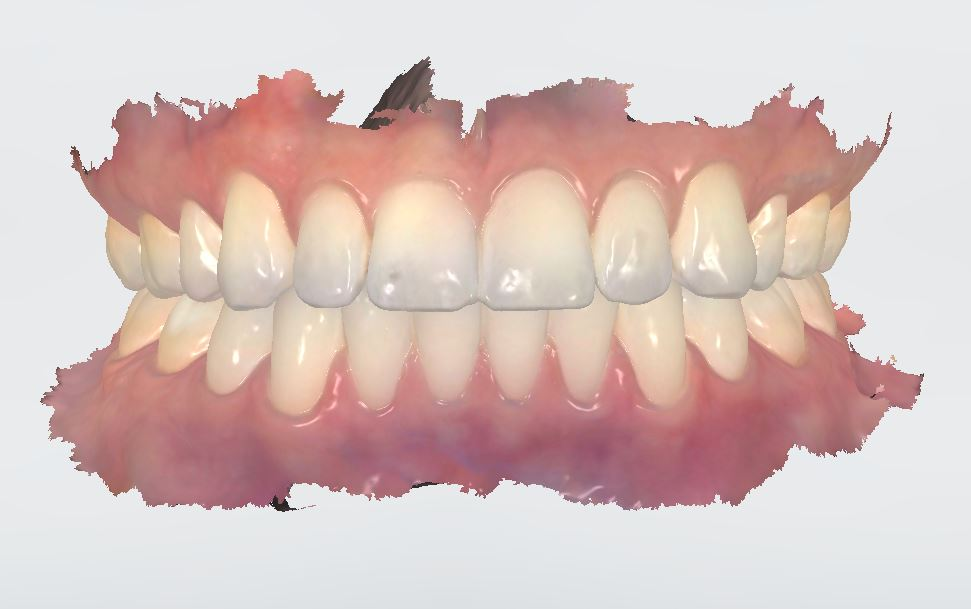

Orthodontist Proposal

After all materials are gathered, an orthodontist creates the movement proposal for the doctors approval. This is done through an on-line link that can be viewed in each stage of the process in 3D. Changes can be requested as needed or the proposal is approved for production.

Placeholder Picture